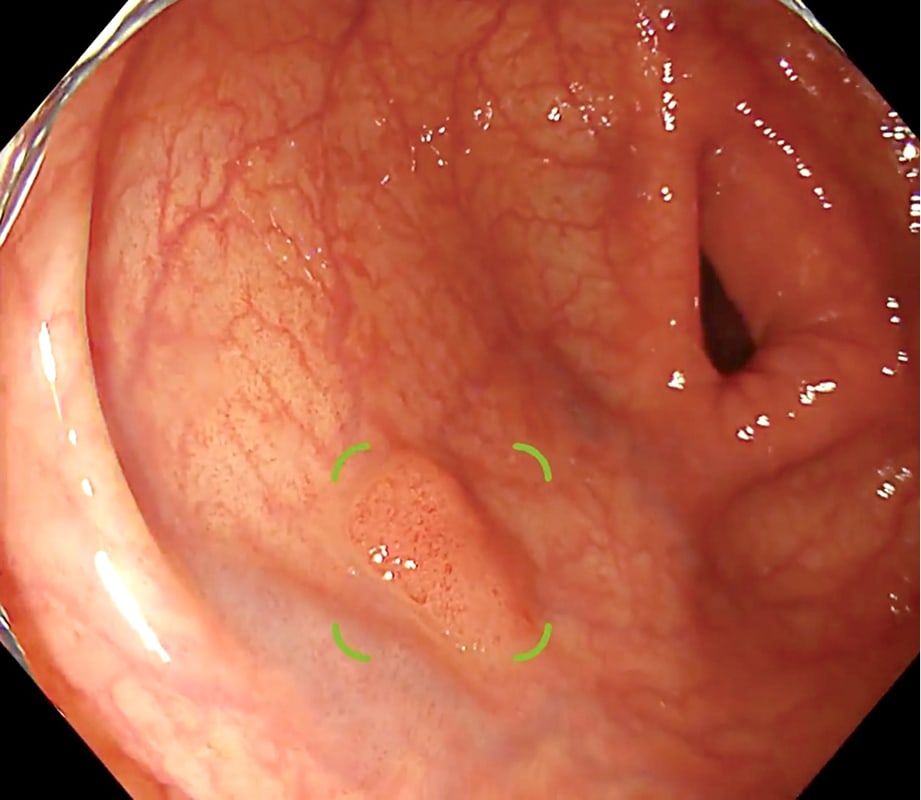

大腸ポリープ候補*を検出し、

大腸内視鏡検査を支援する

大腸内視鏡検査中に通常白色光モードにおいて入力された大腸内視鏡画像情報から、大腸ポリープ候補を検出することが出来ます。検出した場合には、メイン画像の四隅を囲むアラート枠を表示した後、ポリープ候補領域の四隅を囲む矩形を表示します。

* 隆起型及び表面型(表面隆起型)